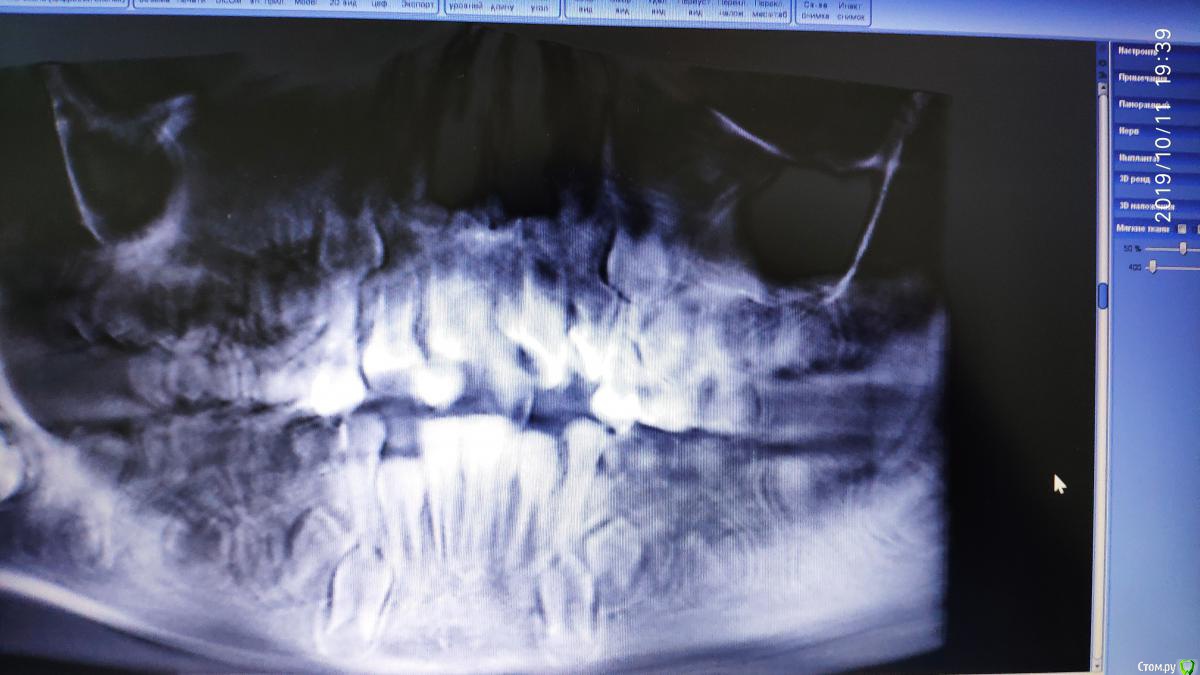

dr.i Опубликовано 11 октября, 2019 Поделиться Опубликовано 11 октября, 2019 (изменено) Нужна помощь в определении как быть в этой ситуации мне кажется здесь сверхкомплектные зубы,и скорее на удаление пойдут эти два зуба.что можете сказать по этому поводу. Изменено 11 октября, 2019 пользователем dr.i Ссылка на комментарий